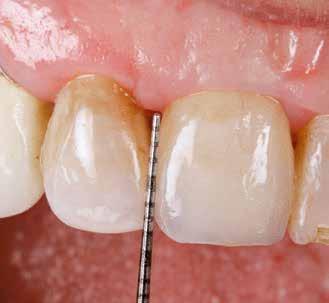

Preoperatív helyzet

Egy fiatal páciens jelentkezett nálunk, akinek eltörött a szabad véggel rendelkező hídja (1. ábra). A hiányzó, első premoláris fog esetén implantációs pótlást javasoltunk. A csontállomány értékeléséhez CBCT-vizsgálatot végeztünk, és az elemzéséhez NNT Viewert (NewTom) használtunk, és copaSKY 4×10 mm-es (bredent medical) implantátumot választottuk a fog pótlásához

1. ábra: Műtét előtti fogászati panorámafelvétel, amelyen a hiányzó felső állcsont jobb első premolárisát és a szabad véggel rendelkező hidat láthatjuk. — 2. ábra: Az implantátum méreteinek megtervezése CBCT-vel. 3. ábra: Bukkális lágyrészdefektus. — 4. ábra: A biológiai szélesség értékelése a vertikális lágyszövetvastagság alapján. 5. ábra: Palatinális „tekercslebeny” – Palatal roll flap. — 6. ábra: Bredent medical copaSKY 4x10 implantátumbeültetés. 7. ábra: Szubkresztális implantátumbeültetés a várható biológiai szélességnek megfelelően.

(2. ábra). A lágyszövetek értékelése Seibert szerinti I. osztályú csontdefektust állapított meg (3. ábra), ezért a beavatkozáskor palatinális „tekercslebenyt” preparáltunk (palatal roll flap), és implantációt végeztünk, hogy kompenzálni tudjuk a bukkális lágyszövet-behúzódást. Megmértük a vertikális lágyszövetvastagságot, és úgy terveztük, hogy a szubkresztális implantátum beültetése összhangban legyen a biológiai szélesség kialakulásával a transzgingivális gyógyulási periódus alatt (4. ábra)